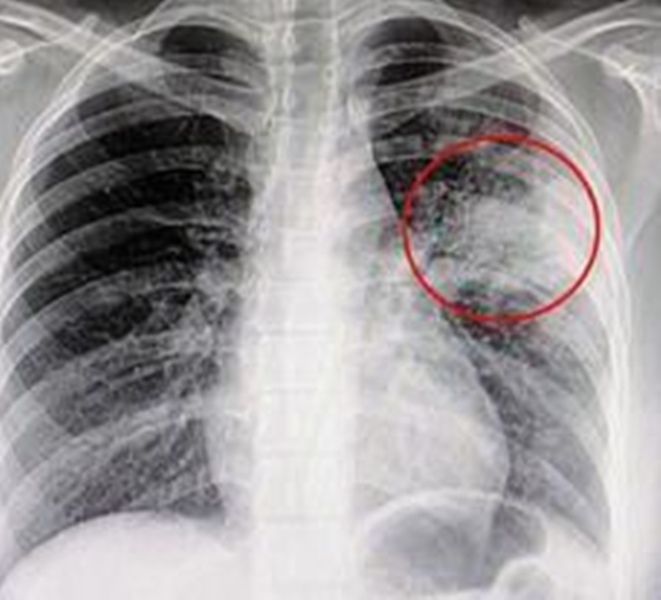

在谈及技术创新时,沈桂贤披露砂拉越再次走在全国最前沿。民都鲁卫生局近日获本地企业慷慨解囊,率先引入了全马首台手持式X光机。这项技术起源于军事用途,如今在婆罗洲丛林中焕发新生,成为了医疗团队深入内陆长屋进行实地筛查的“秘密武器”。

根据《诗华日报》报道他解释,传统的检查方式需要动员整座长屋的居民前往市区诊所,舟车劳顿之余更增加了沿途交叉感染的风险。如今,医疗团队只需携带这台轻便设备,便能实现“就地筛查、就地诊断”,极大地缩短了阻断传染链的时间。